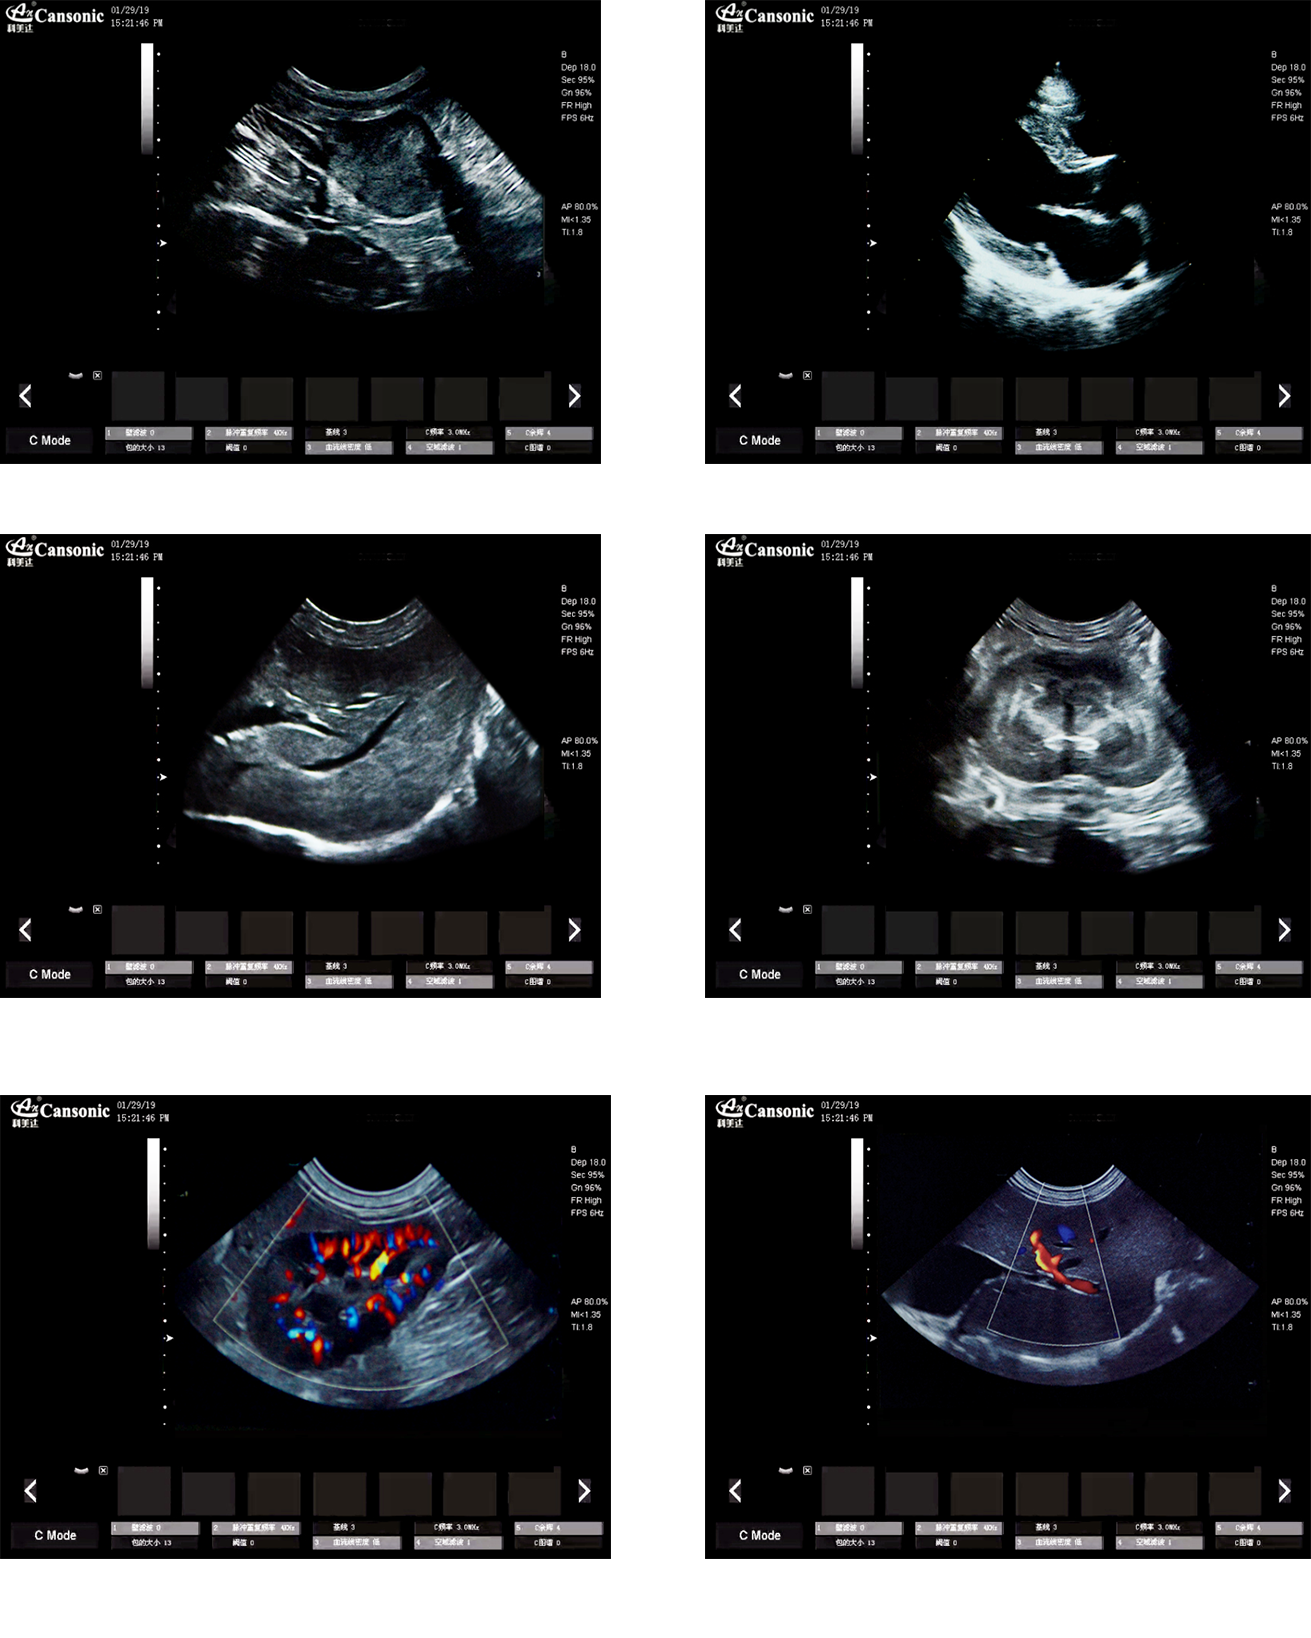

臨床圖示

1、薈萃高端彩超的專業(yè)技術(shù),各類型的專業(yè)獸用探頭,提供完整的動物臨床診療方案

2、專業(yè)的獸用彩超軟件,適合犬、貓、馬、牛、羊等各類大小動物彩超檢查

3、完備的獸用高端功能,能量多普勒POWER模式彩色多普勒Color成像模式